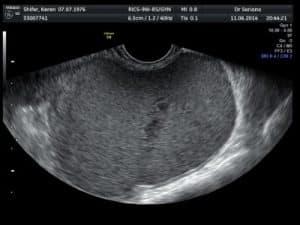

לפני החלטה על טיפול יש להכיר לעומק את עברך הרפואי והמשפחתי, עברך המיילדותי, תוכניות הילודה ולבצע בדיקה גופנית מלאה, כולל בדיקה גינקולוגית ובדיקת אולטרסאונד אגן  וזאת על מנת להעריך מה הסיבה לדימום המוגבר. במהלך הבירור יש להשלים בדיקות נוספות:

• אולטראסאונד ייעודי מקיף